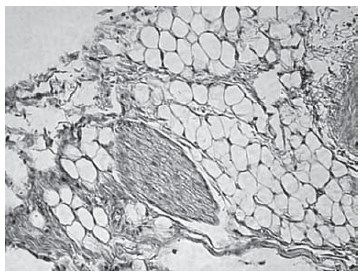

При гистологическом анализе изъятого материала (спинномозговых нервов и их чувствительных узлов крыс) на 2-е сутки после проведения радиочастотной импульсной модуляции визуализированы фрагменты чувствительных спинномозговых нервов типового строения с выраженным отеком, являющимся результатом травмирования. Дистрофических и деструктивных изменений не выявлено (рис. 3).

Рис. 3. Чувствительный узел спинномозгового нерва спустя 2 суток после воздействия. Окр. гематоксилин + эозин, ув.×200